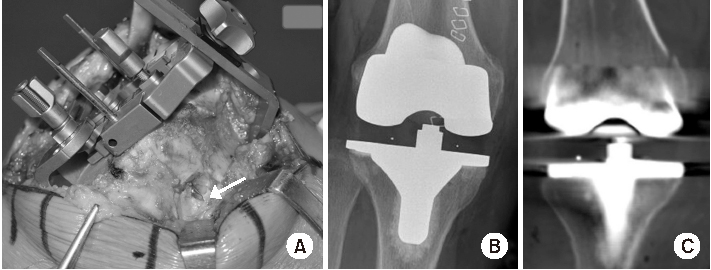

A 59-year-old female patient received TKA with the e.motion® pro knee system (Aesculap). The patient's T-score was -1.3 (L1-4) and 0.1 (femur total). BMI was 28.4 kg/m2. She was diagnosed with osteoarthritis and did not have any other history. The surgery was performed with the same procedure. During surgery, we inspected the medial femoral condyle carefully for demonstrating a cortical perforation. After distal femur cutting, the femoral anteroposterior (A/P) and rotational block was secured with the medial and lateral pins. The sharp tip of medial pin was palpable. The soft tissue covered it was removed and the pin perforation was identified (Fig. 2A). Pin perforation made a hole. We also identified that postoperative radiologic findings on radiograph and CT scan were same to case 1 (Fig. 2B, C).